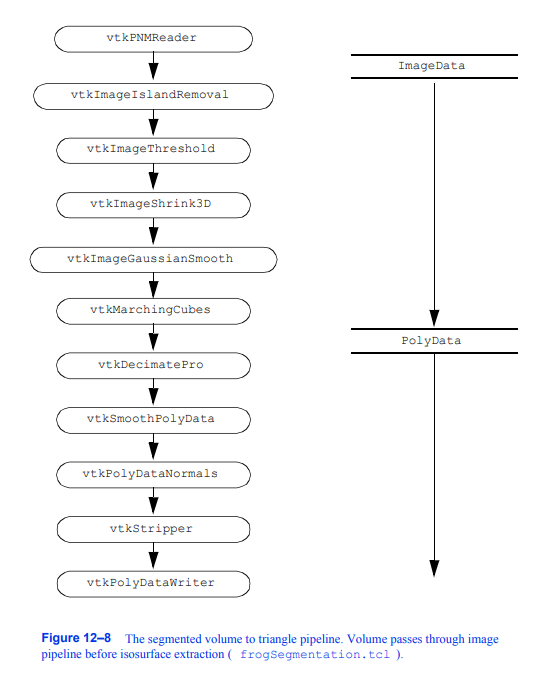

管路概述管路设计

如图12 - 8所示。多年来,我们实验室和布里格姆妇女医院手术计划实验室一直在开发这种通用管道。我们发现它能从分段数据集中产生合理的模型。不要被过滤器的数量吓倒(总共12个)。在开发VTK之前,我们用一堆用不同接口编写的程序做了类似的处理。我们使用中间文件将数据从一个过滤器传递到下一个过滤器。在VTK中实现的新管道在时间和计算资源上更加高效。

图12-8分段卷转三角管路在等值面提取(frogSegmentation)之前,体积通过图像管道。tcl)。